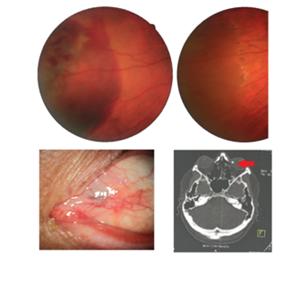

Intraocular Foreign Body

Jul 18 2022 by Nelson Chamma Capelanes, MD

Intraocular foreign body after stone trauma. Foreign body is found in the choroid. - Fundus image on the upper left: one day after the trauma showing subretinal and intraretinal hemorrhage - Fundus image on the upper right: 40 days after laser photocoagulation. - Lower left image: 30 days after the trauma, showing part of the foreign body in the nasal region. - Lower right image showing CT scan and intraocular foreign body location.

Photographer: Nelson Chamma Capelanes, Promacula Indaiatuba, Brazil

Imaging device: Canon CX-2

Condition/keywords: intraocular foreign body